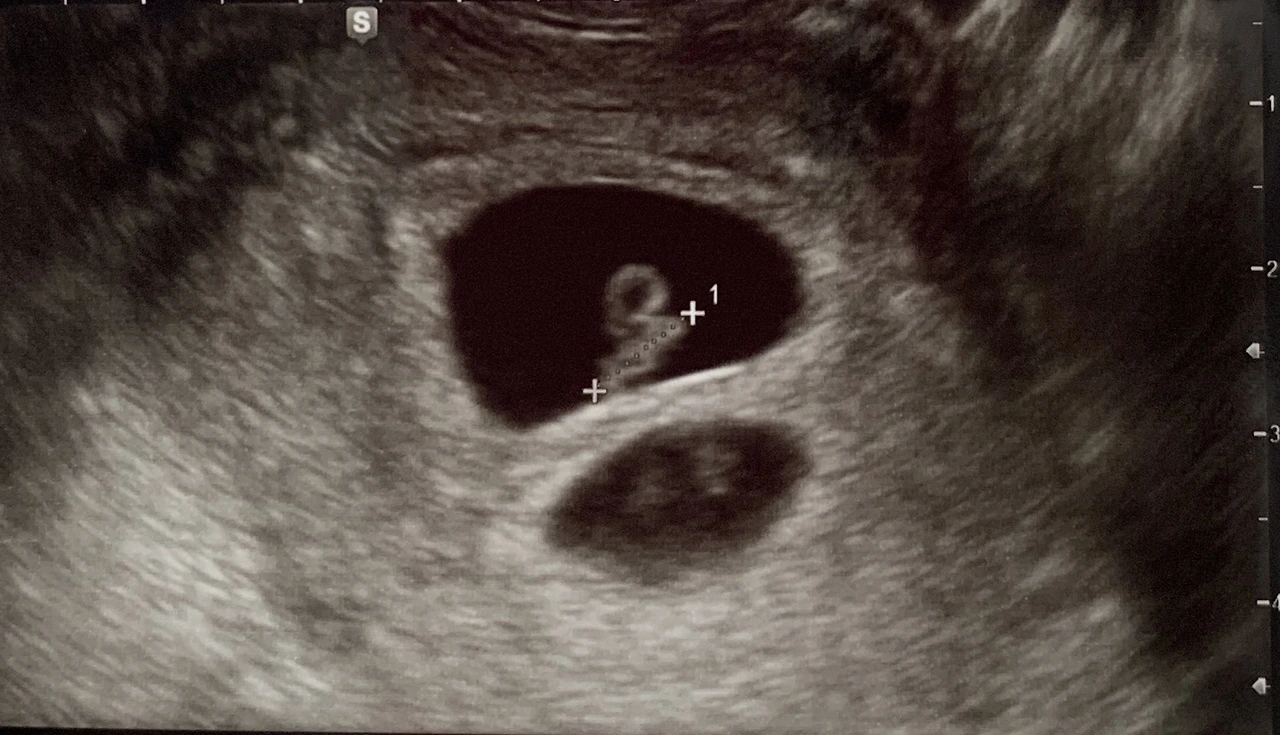

늘 그렇듯이 오랜 대기 시간 끝에 초음파실로 들어가 설레는 마음으로 모니터 화면을 보고 있었다.

담당 의사 선생님은 "어? 어? 아기집이 두 개네요?"

"네 아기집이 두 개인 이란성쌍둥이예요."

의사는 예정과 달리 두 명의 심장소리를 들려주었다.

쌍둥이초음파.jpeg 두 개의 아기집 - 내 두 명의 아기들

35세 이상이라 시험관 시술로 배아를 3개를 이식하기 때문에 최대 세 쌍둥이가 가능은 하지만, 그동안 한 명도 되지 않던 임신이 두 명이 되다니.. 생각지도 못한 일이 벌어졌다.